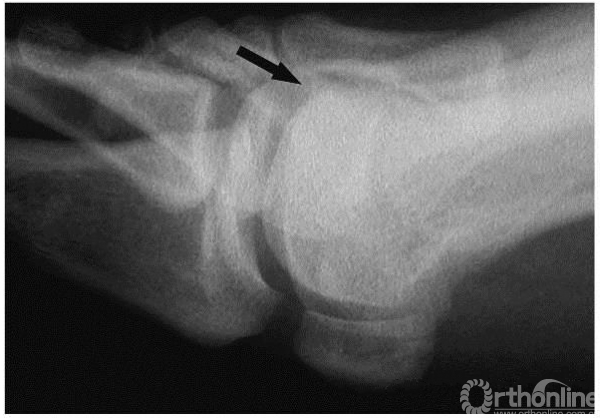

1期:正位x线上,箭头示外侧小的骨赘形成,关节间隙完好

1期:侧位x线上,箭头示小的背侧骨赘